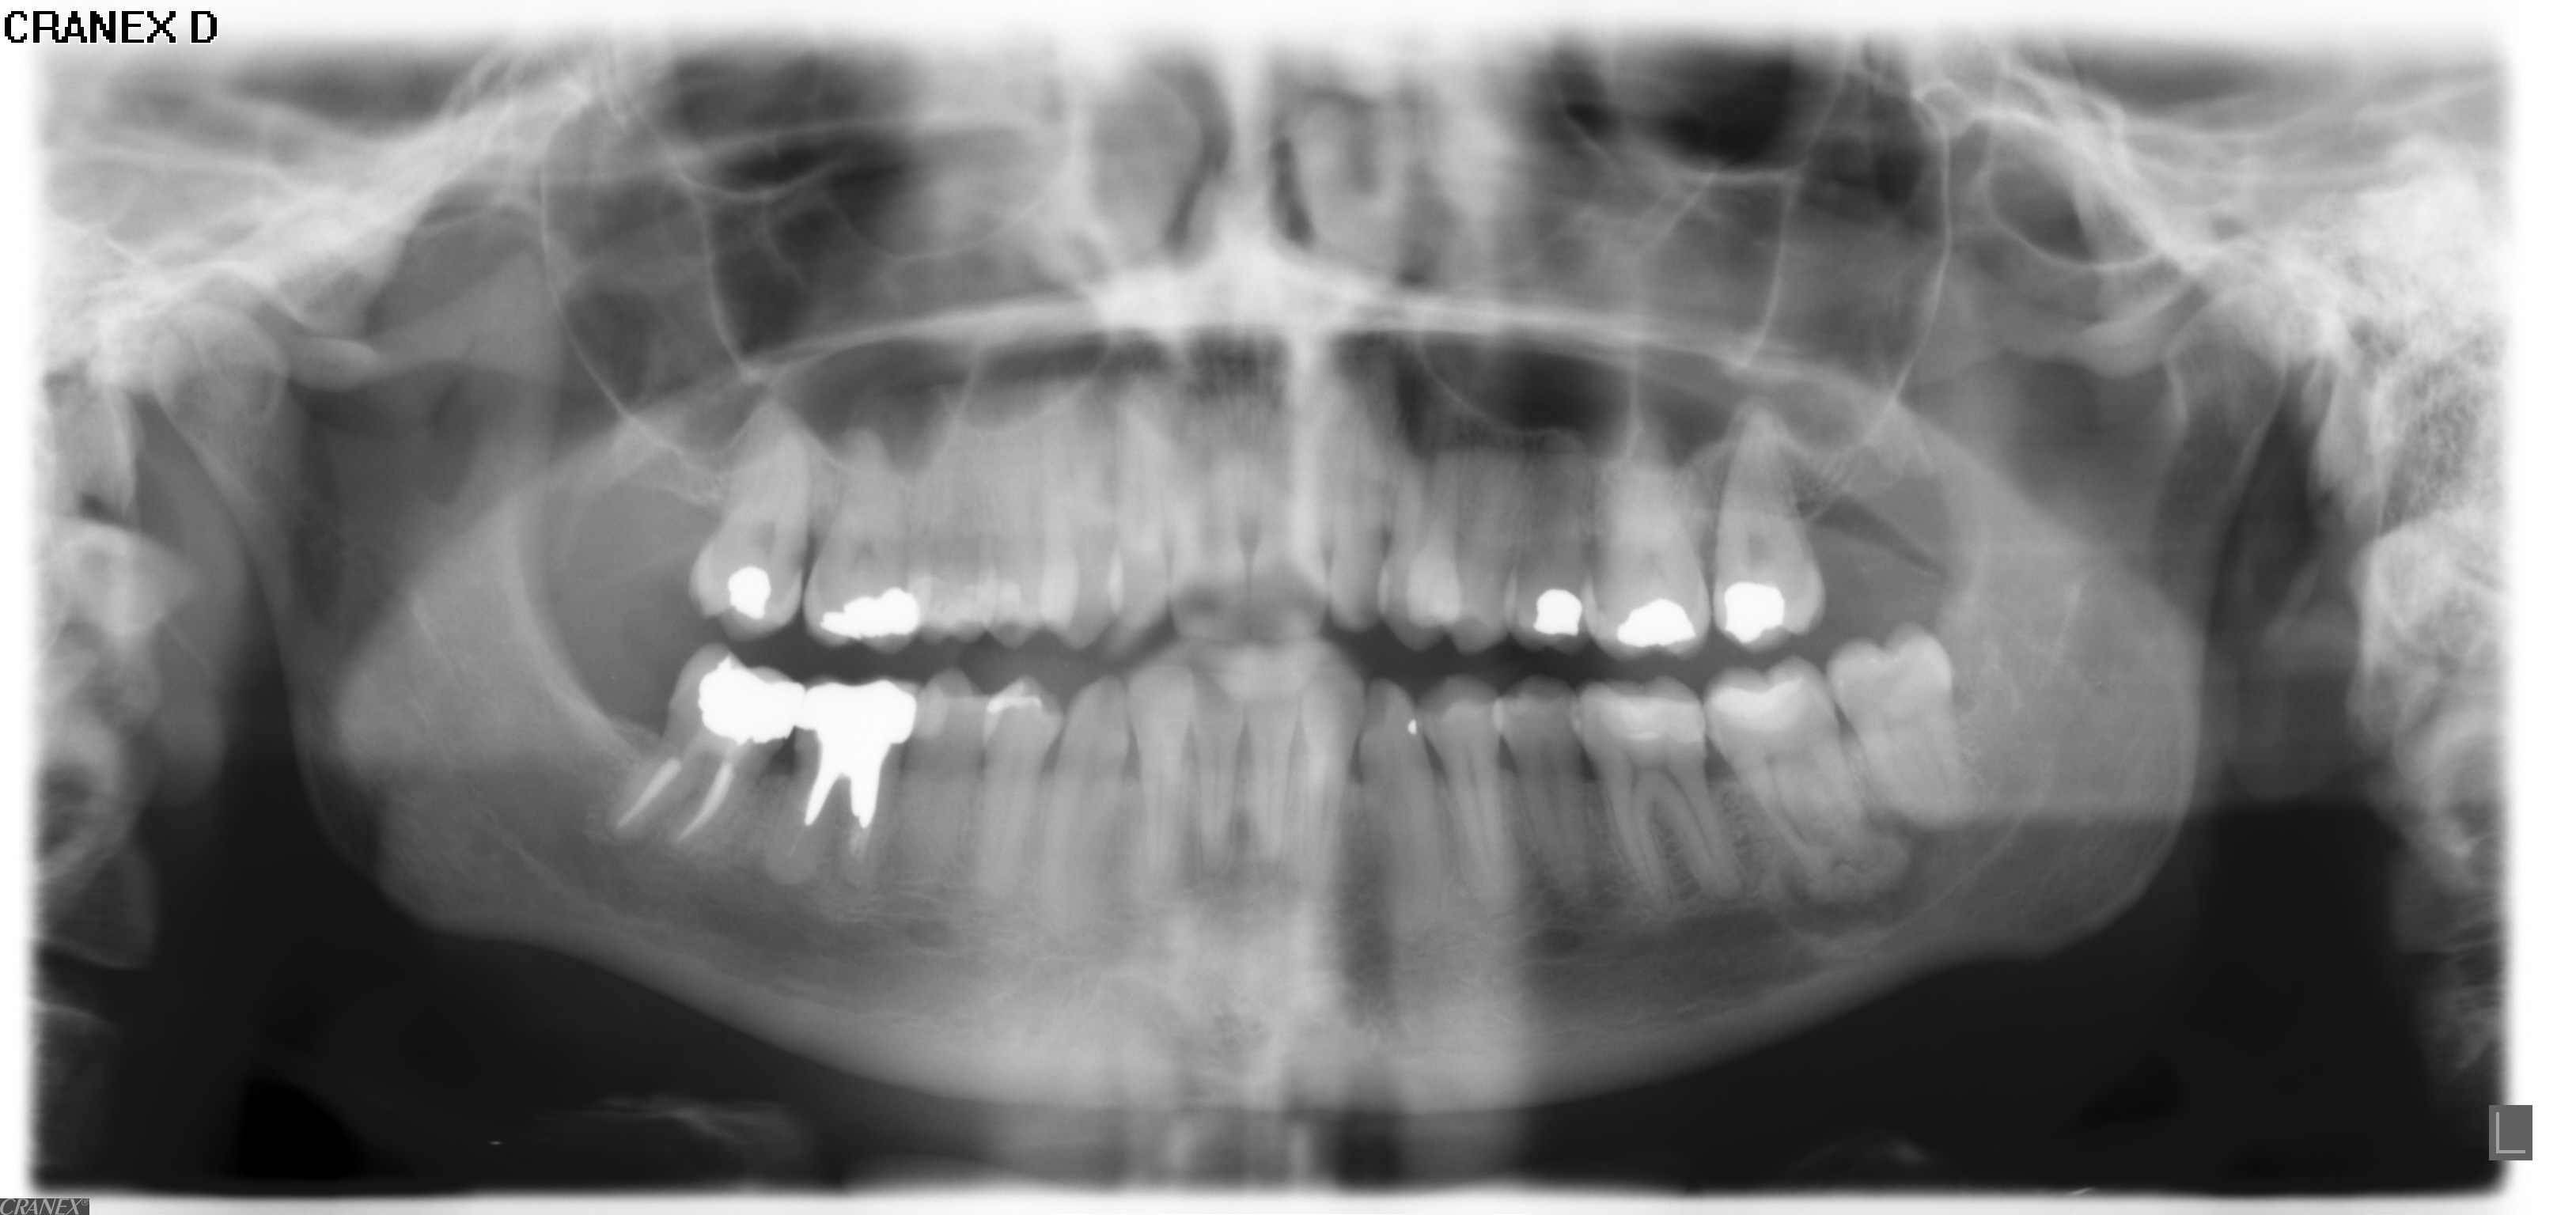

Normalmente ha senso rifare una vecchia otturazione in amalgama?